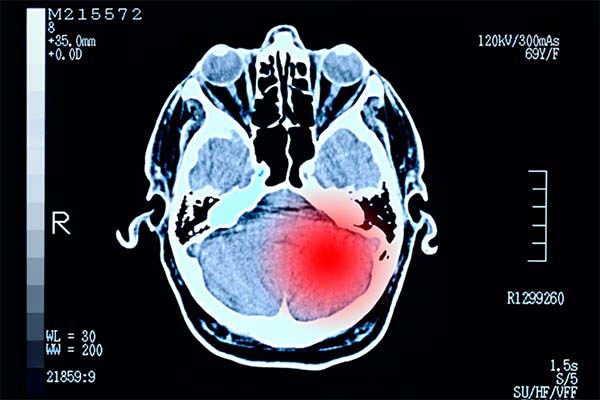

A tudósok áttörést értek el a halálos agydaganatok elleni küzdelemben, miután kifejlesztettek egy genetikailag módosított vírust, amely vadászik és elpusztítja a daganatokat.

Az orvostudomány számára jelentős előrelépést jelentve, a szakértők megtalálták a módját a glioblasztóma – a betegség egyik legagresszívabb formájának – páncéljának feltörésére. Egyetlen módosított vírus injekció beadásával az orvosok mostantól képesek beindítani a szervezet saját immunrendszerét, hogy az behatoljon a rákos sejtekbe és elpusztítsa azokat.

A Mass General Brigham és a Dana-Farber Rákkutató Intézet szakértői által kifejlesztett forradalmi kezelés egy onkolitikus vírust használ – a herpes simplex vírus laboratóriumban módosított változatát. A glioblasztóma régóta rémálom az orvosok számára, mivel egy „hideg” daganat, ami azt jelenti, hogy gyakorlatilag elrejtőzik a szervezet természetes védekező rendszerei elől.

Dr. Kai Wucherpfennig, a Dana-Farber Rákkutató Intézet munkatársa elmondta: „A glioblasztómában szenvedő betegek nem részesültek előnyben az immunterápiákból, amelyek átalakították a betegellátást más ráktípusok, például a melanoma esetében, mivel a glioblasztóma egy „hideg” daganat, amelybe a rák ellen küzdő immunsejtek rosszul infiltrálódnak. Klinikai vizsgálatunk és mechanisztikus tanulmányunk eredményei azt mutatják, hogy most már megvalósítható ezeknek a kritikus immunsejteknek a glioblasztómába juttatása.” Beadás után a vírus csak a rákos sejtekben szaporodik, ami azok pusztulását okozza, miközben az egészséges agyszövet teljesen érintetlen marad.

Egy 41, kiújult rákos beteg bevonásával végzett klinikai vizsgálatban megdöbbentő eredmények születtek. A kezelés nemcsak közvetlenül pusztította el a sejteket, hanem mélyen az agyba hívta a T-sejteket, ahol azok folytatták a küzdelmet.

A Cell folyóiratban megjelent adatok szerint a betegek a vártnál tovább éltek, különösen azok, akiknél már voltak antitestek a vírussal szemben. E. Antonio Chiocca, MD, PhD, a Massachusetts General Brigham kórházból elmondta, hogy a felfedezés véget vethet a rákkezelés 20 éves patthelyzetének. Azt mondta: „Kimutatjuk, hogy a tumorsejteket támadó T-sejtek fokozott beszűrődése terápiás előnyhöz juttatja a glioblasztómás betegeket.”

„Eredményeink fontos következményekkel járhatnak egy olyan rákos megbetegedés esetében, amelynek ellátási standardja 20 éve nem változott.” A kutatók azt találták, hogy minél közelebb voltak a T-sejtek a haldokló rákhoz, annál tovább élt a beteg, ami arra utal, hogy a szervezet saját immunrendszere végre megkapja az eszközöket az agydaganatok elleni háború megnyeréséhez.